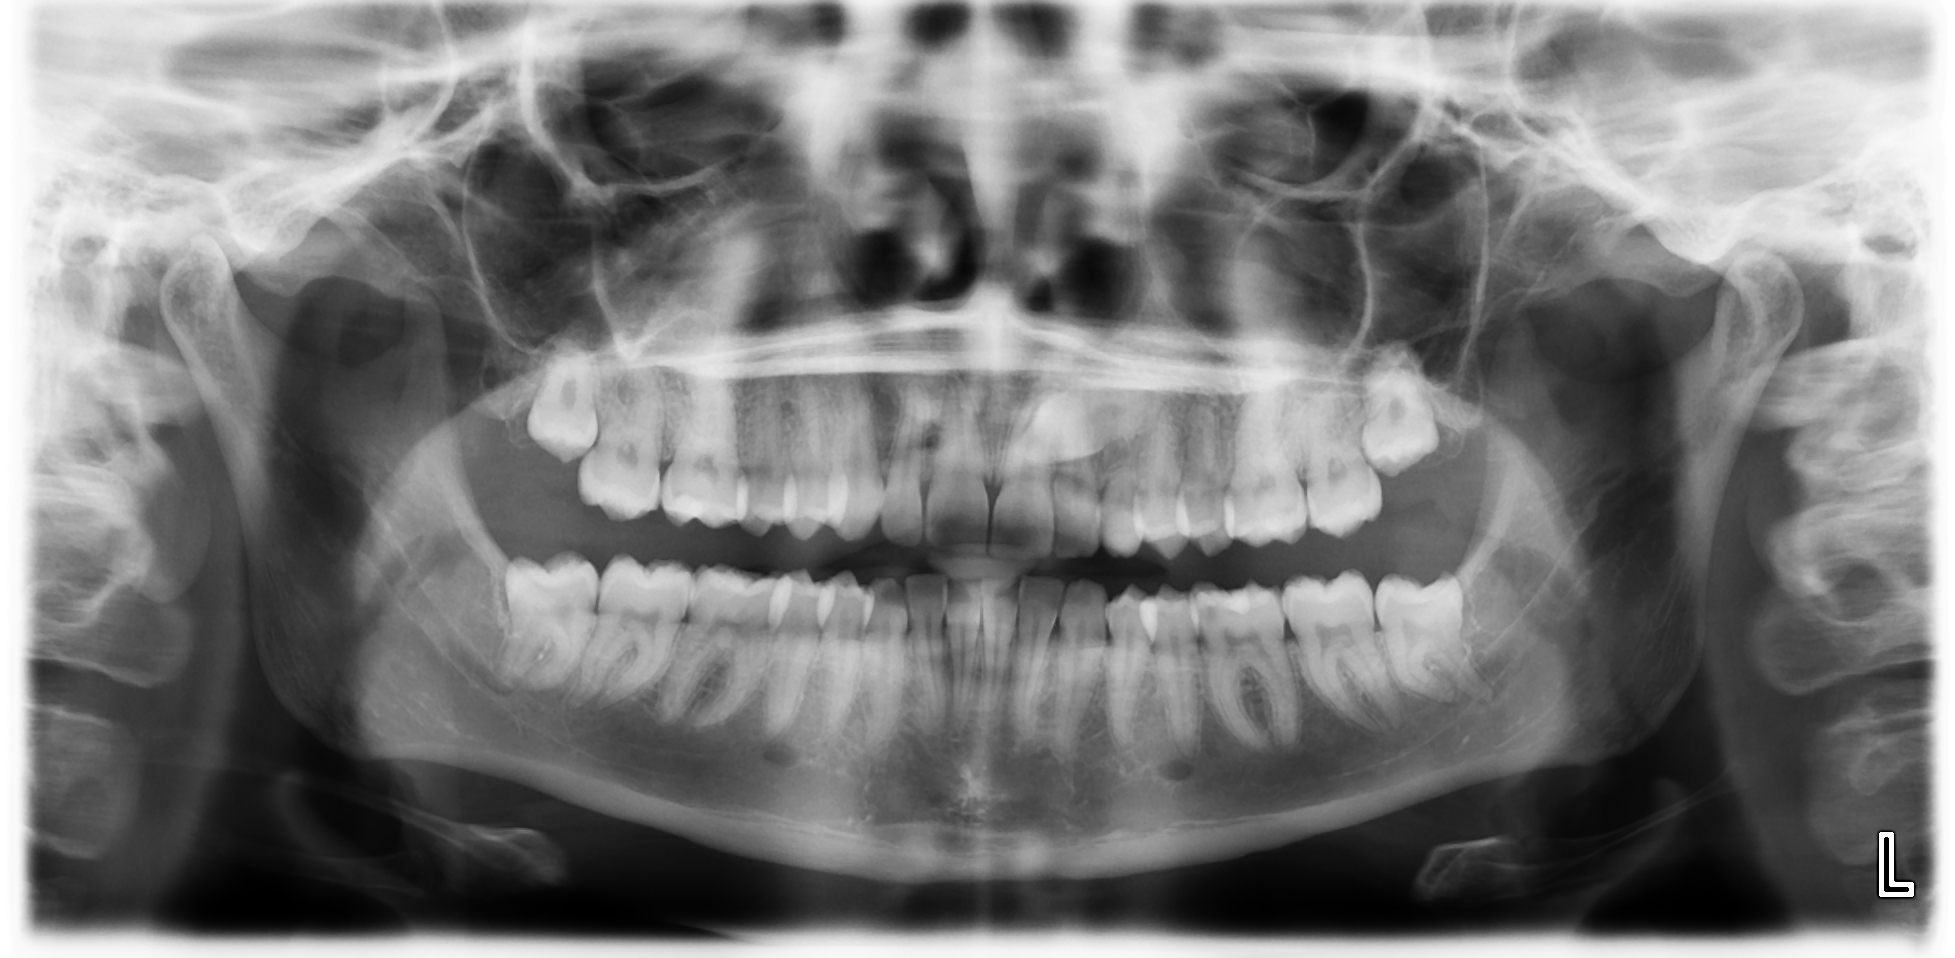

OPTG eli koko leuan rtg kuva alkutilanteesta

Alkutilanne ennen kevytsiltaa. Kulmahammas poikittain syvällä luun sisällä, maitohammas pysyvän kulmahampaan paikalla. Hoidon aikana molemmat poistettu. Ja implantti asetettu paikoilleen